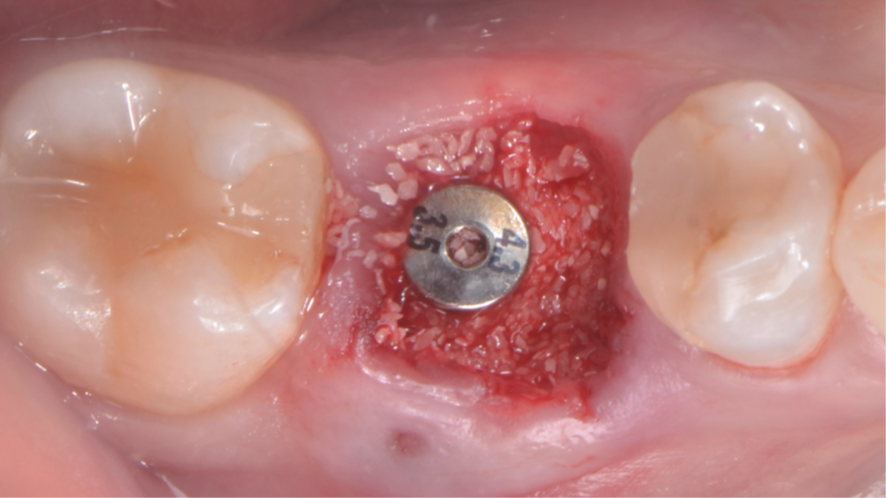

Após a instalação do implante, um cicatrizador foi colocado somente para proteger a conexão morse do implante e o GAP foi preenchido com Extra Graft 1g (Figura 7). Como foi alcançada uma alta estabilidade primária, um pilar provisório de titânio foi instalado e nele foi confeccionado um cicatrizador personalizado com resina fluida (Figuras 8, 9 e 10).